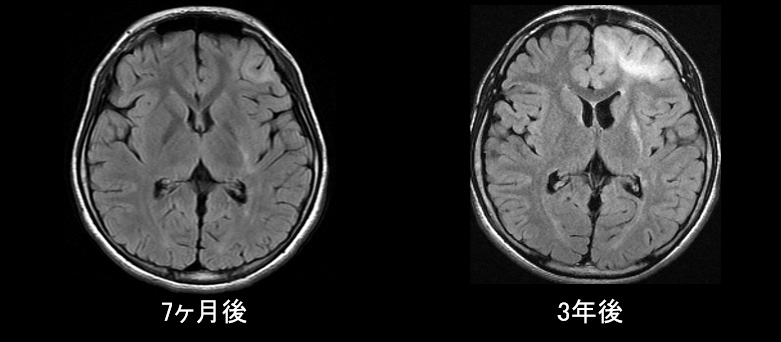

• 左基底核のT2WI/FLAIRでの高信号、ADC上昇

• 経過中に左前頭葉にT2WI/FLAIR高信号域が出現、左基底核が萎縮

定期的なγグロブリン治療、抗てんかん薬内服で加療していた。この間、MRは基底核萎縮の進行以外に変化は無かった。吃音や右手関節・足関節の背屈制限は徐々に進行した。

初診から3年後のMRで左前頭葉のT2WI/FLAIR高信号域の拡大が認められたため、脳生検を行った。